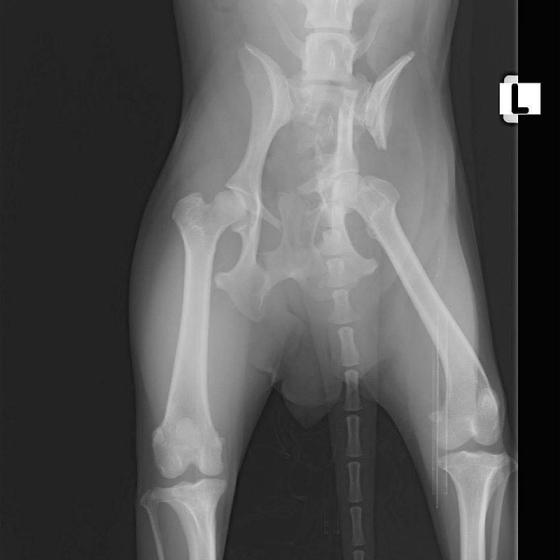

Bola neskutočne zanedbaná, hladná a dolámaná. Panvu má zlomenú na troch miestach, od úderu jej praskol močový mechúr a mala na sebe snáď všetky blchy sveta, žrali ju zaživa. Zotavuje sa.. Pomaličky, ale zotavuje sa po náročných operáciách a dúfame, že bude opäť v poriadku. Bude potrebovať rehabilitovať, aby vedela opäť behať, ale zabezpečíme jej úplne všetko, čo bude treba!!